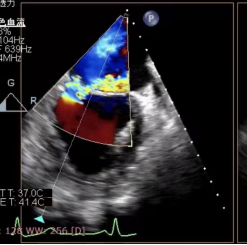

检查显示二尖瓣重度返流

被送到哈医大二院急诊科后,孙先生的病情急转直下,急诊科立即组织抢救,同时边抢救边转入心内科重症监护室,监护室杨爽主任医师和刘芳副主任医师立即组织抢救、麻醉、气管插管、有创呼吸机支持,并给予药物维持生命体征,经过一番抢救后,患者情况暂时控制住了。另一边,心内科导管室手术陈涛副主任医师和杨光副主任医师,对患者病情进行评估并立即向于波汇报,在于波指导协调下,对患者进行了急诊冠脉造影排除冠脉疾病,同时在超声医学科副主任冷晓萍教授团队的配合下进行急诊食道超声,最终诊断患者是由于腱索断裂导致二尖瓣后叶脱垂造成二尖瓣重度返流,最终导致急性肺水肿,低血压休克。